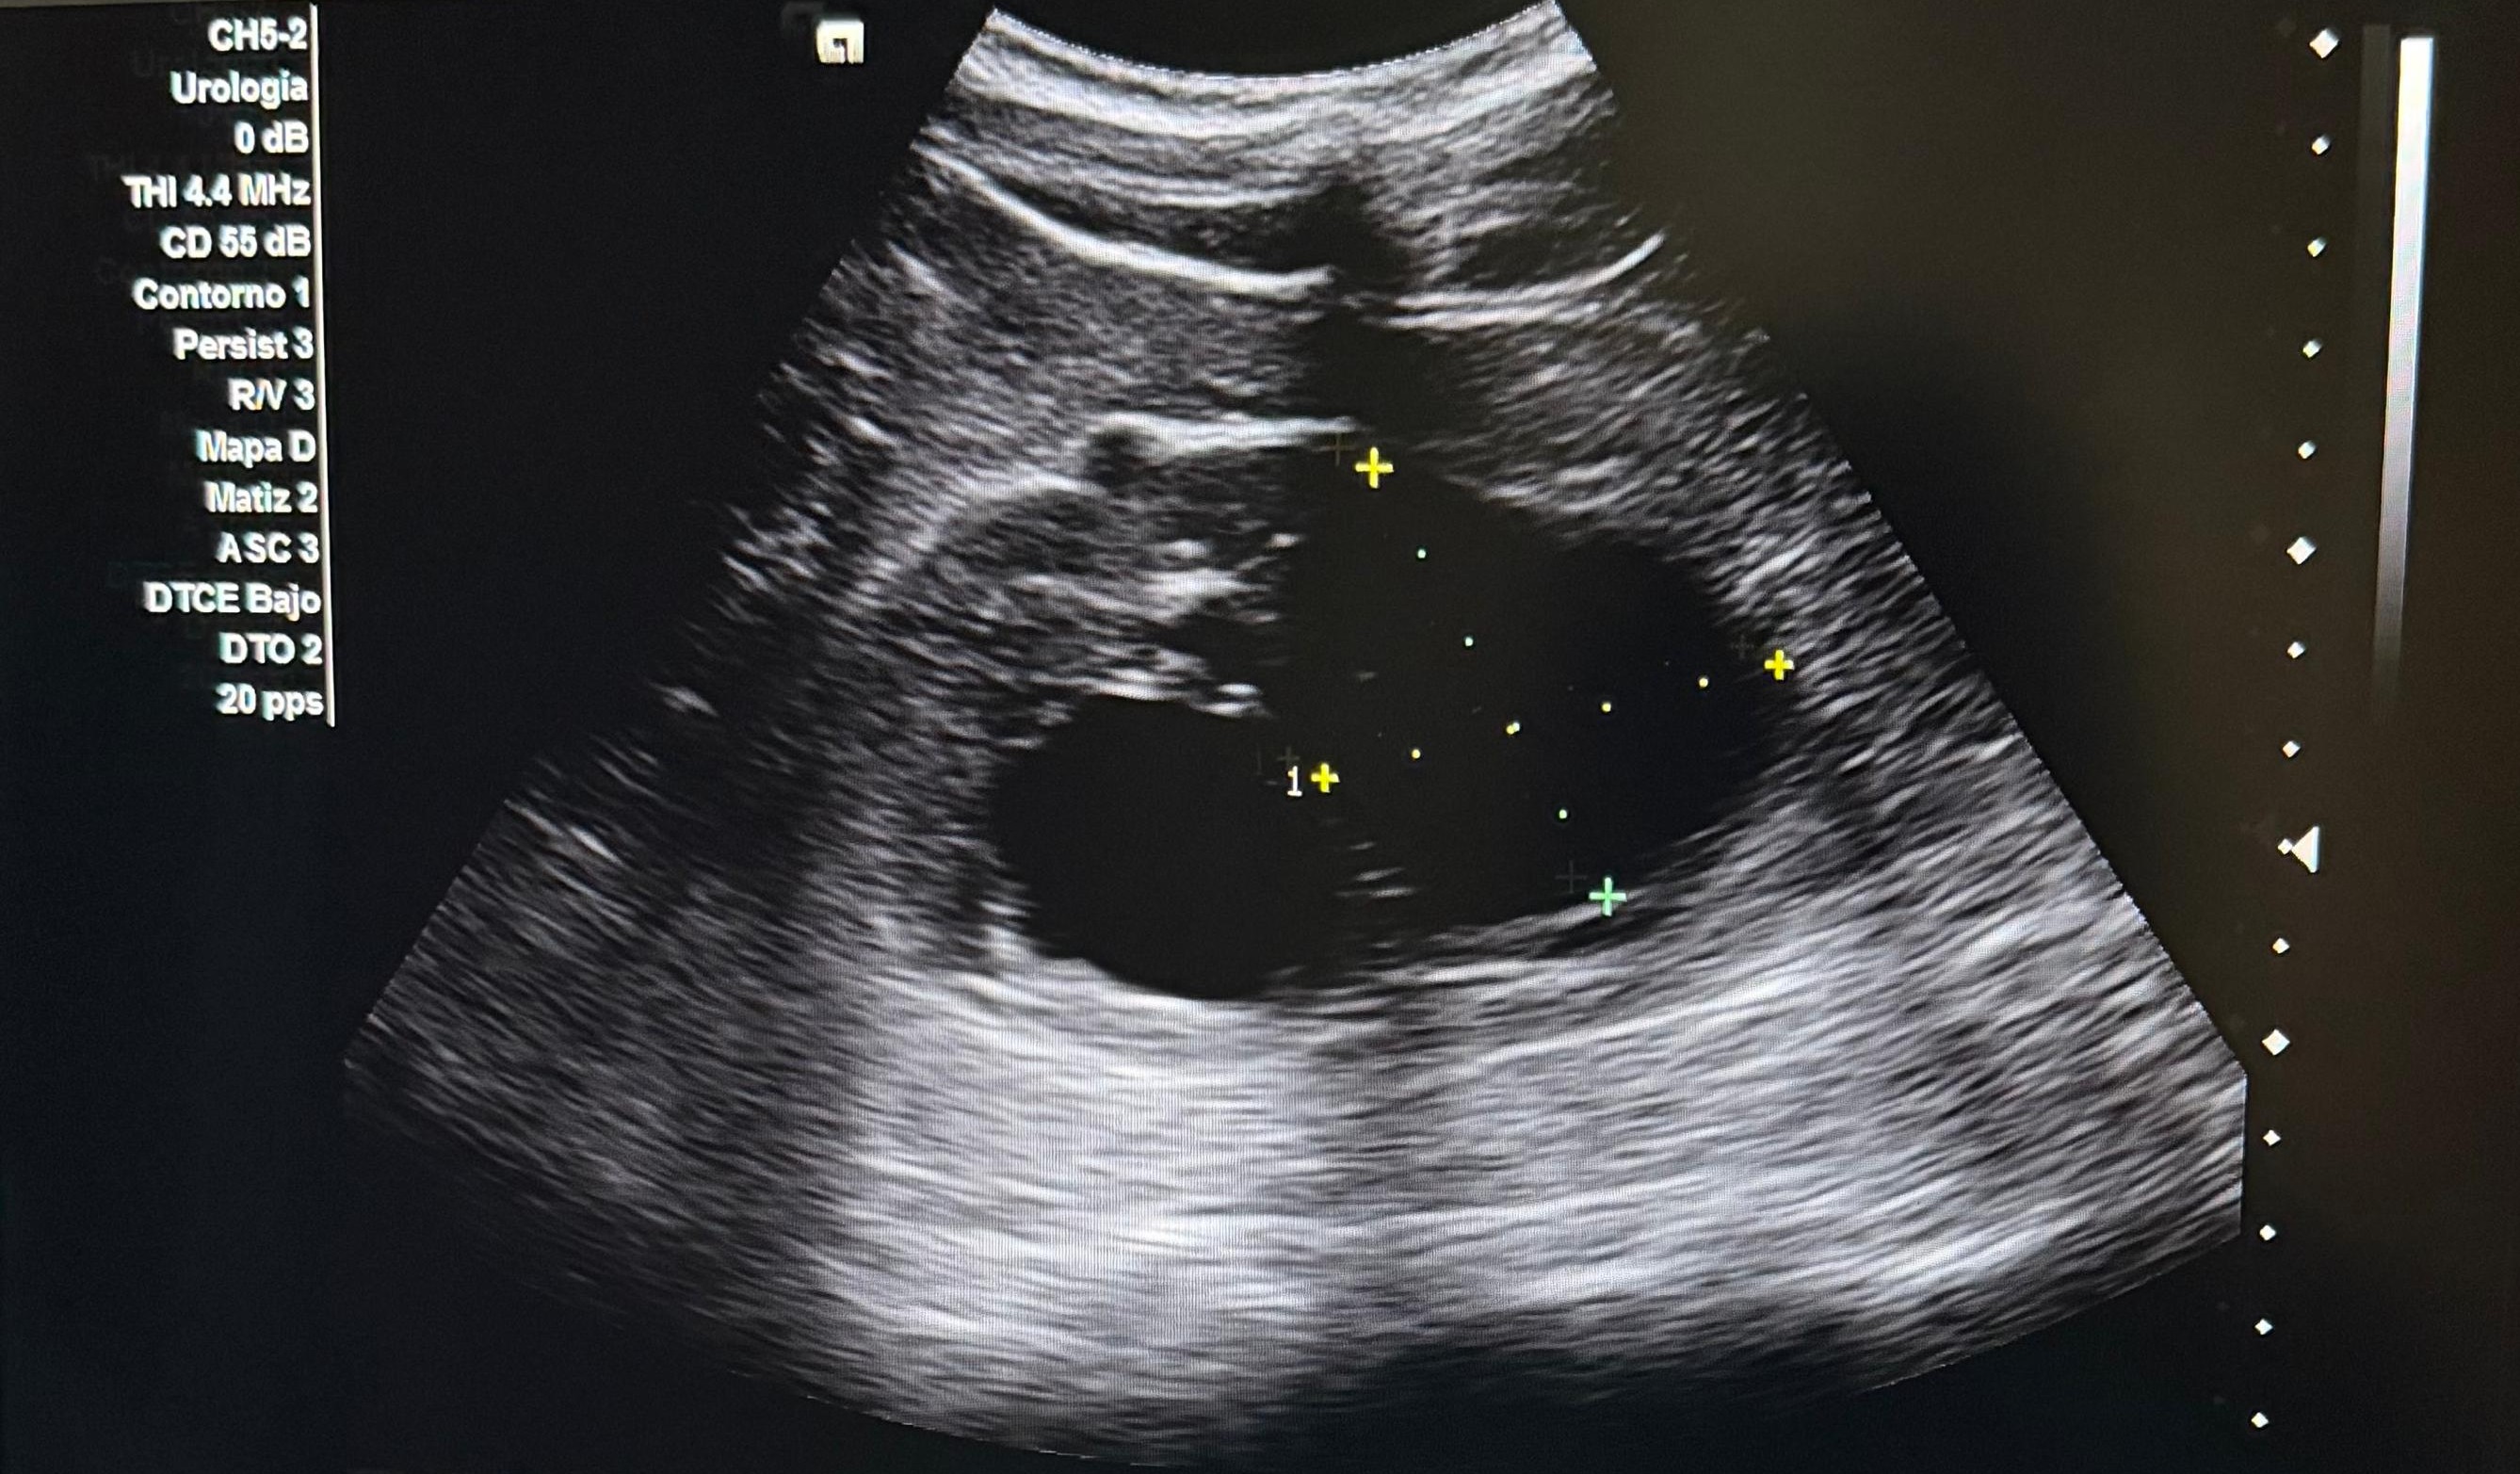

Hallazgos ecográficos

Se realiza ecografía abdominopélvica donde se visualiza vejiga sin alteraciones, próstata aumentada de tamaño con un volumen estimado de 59 cc. Como hallazgo incidental se objetivan ambos riñones aumentados de tamaño con varios quistes.

Juicio clínico: HBP y hallazgos compatibles con quistes simples vs poliquistosis renal.